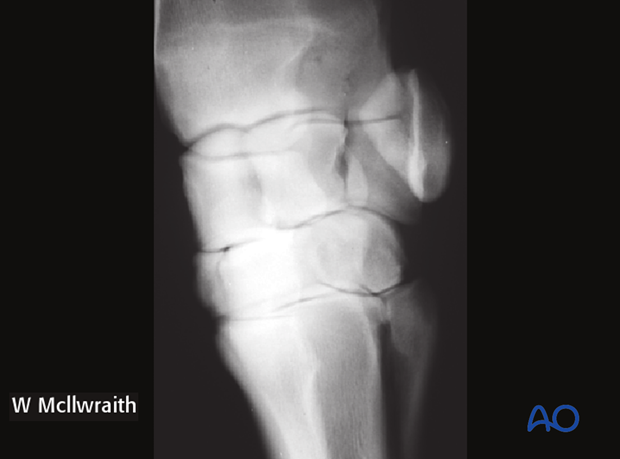

Frontal fractures of the radial facet of the third carpal bone can be non-displaced or displaced. Both instances present with lameness and joint effusion. The nature of the fracture is confirmed with radiographs.

These fractures are demonstrated with:

This x-ray shows a complete non-displaced fracture in the DL-PmMO view.